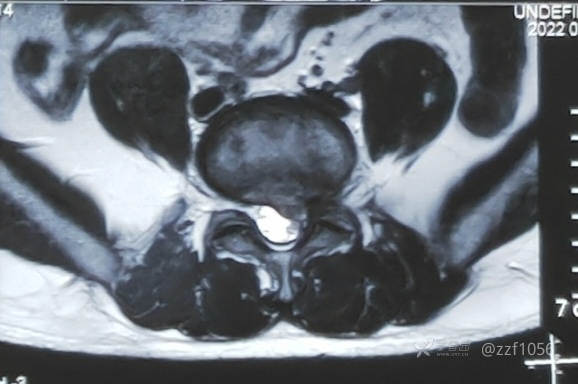

先睹影像

脱出明显

左侧,貌似两块